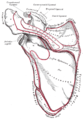

السطح العلوي يتوجه لأعلى ، وإلى الوراء، ونحو الجانب الوحشي ، وهو محدب و خشن، ويتصل علي بعضه ألياف العضلة المثلثة (الدالية)، وفي بقية مداه يتغطي بنسيج تحت الجلد إنگليزية: Subcutaneous tissue. سطحه السفلي ناعم ومقعر.[1]

الحواف

الحافة الجانبية الوحشية سميكة وغير منتظمة، وهناك ثلاث أو أربع حديبات للمنشأ الوتري للعضلة المثلثة (الدالية). حافتها الوسطي الإنسية أقصر من الوحشية وهي مقعرة ، ويتصل عليها جزء من العضلة شبه المنحرفة، وفي وسطهاتقريبا سطح بيضاوي صغير للتمفصل مع النهاية الأخرمية للترقوة.[1]